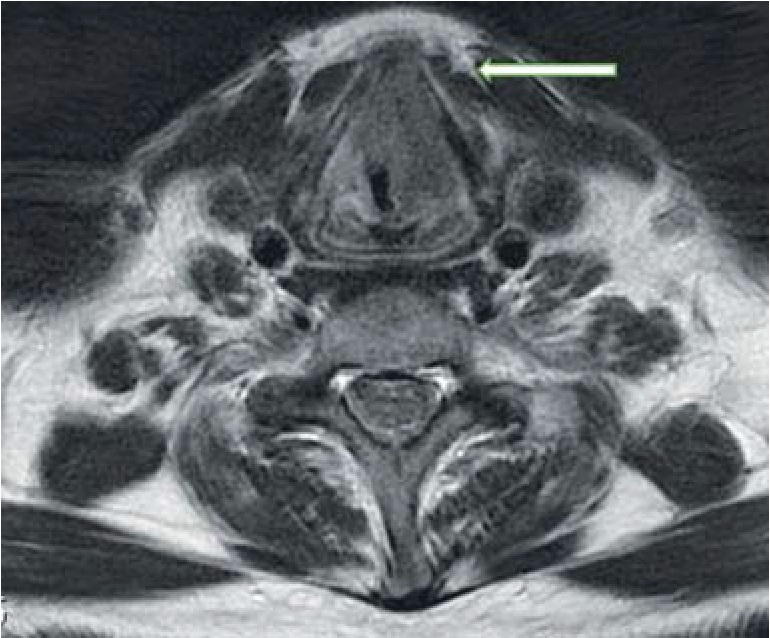

В первой группе у 1 (1,8%) человека в области образования левой голосовой складки, характеризующегося отсутствием гиперинтенсивного сигнала на ДВИ, отмечался гиперметаболизм 18-ФДГ (SUVmax 12,3), а также единичные вторично измененные шейные лимфатические узлы слева с гиперфиксацией РФП в них (SUVmax 8,9), рисунок 4.

Рис. 4. Высокодифференцированный рак гортани с метастазированием в регионарные лимфатические узлы. При ПЭТ/КТ (а) определяется образование в области левой голосовой складки и лимфатический узел III группы слева с повышенным уровнем метаболизма 18-ФДГ, однако при МРТ на ДВИ (б) повышения сигнала в области образования и в области лимфатического узла не отмечается

У 3 человек (5,5%) гиперметаболизма ФДГ в области образований не выявлено, в области лимфатических узлов прослеживался небольшой уровень захвата РФП (SUVmax 2,6), что трактовалось как реактивные воспалительные изменения лимфатических узлов (рис. 5). Воспалительную природу увеличенных шейных лимфатических узлов подтверждало увеличение небных и глоточной миндалин с повышенным уровнем метаболизма глюкозы (SUVmax 5,1).

Рис. 5. Воспалительные изменения правой голосовой складки. При МРТ на Т2-ВИ определяется гиперинтенсивное образование правой голосовой складки (а), характеризующееся отсутствием повышенного сигнала на ДВИ (тонкая белая стрелка) с визуализацией повышенного сигнала в области множественных лимфатических узлов Ia, Ib, IIa, IIb, III, Va групп с обеих сторон (б, в) (толстые стрелки) и в области лимфоидного кольца Пирогова – Вальдейера (голубая стрелка). На ПЭТ/КТ-изображениях (г, д) гиперметаболизма глюкозы в области образования правой голосовой складки не прослеживается (тонкая белая стрелка), в области шейных лимфатических узлов прослеживается небольшой уровень захвата РФП (толстые д стрелки) и повышенный уровень захвата воспалительного характера в области миндалин (голубая стрелка)

В третьей группе у 2 (3,7%) человек также в области выявленной опухоли, изоинтенсивной на ДВИ, прослеживался гиперметаболизм глюкозы (SUVmax 15,7) без сопутствующей лимфоаденопатии (рис. 6). Еще у 2 (3,7 %) пациентов в этой группе гиперфиксации РФП в области образования повышения сигнала на ДВИ не отмечалось, что было расценено как доброкачественные образования с последующей гистологической верификацией опухолей – фиброма и гемангиома (рис. 7).